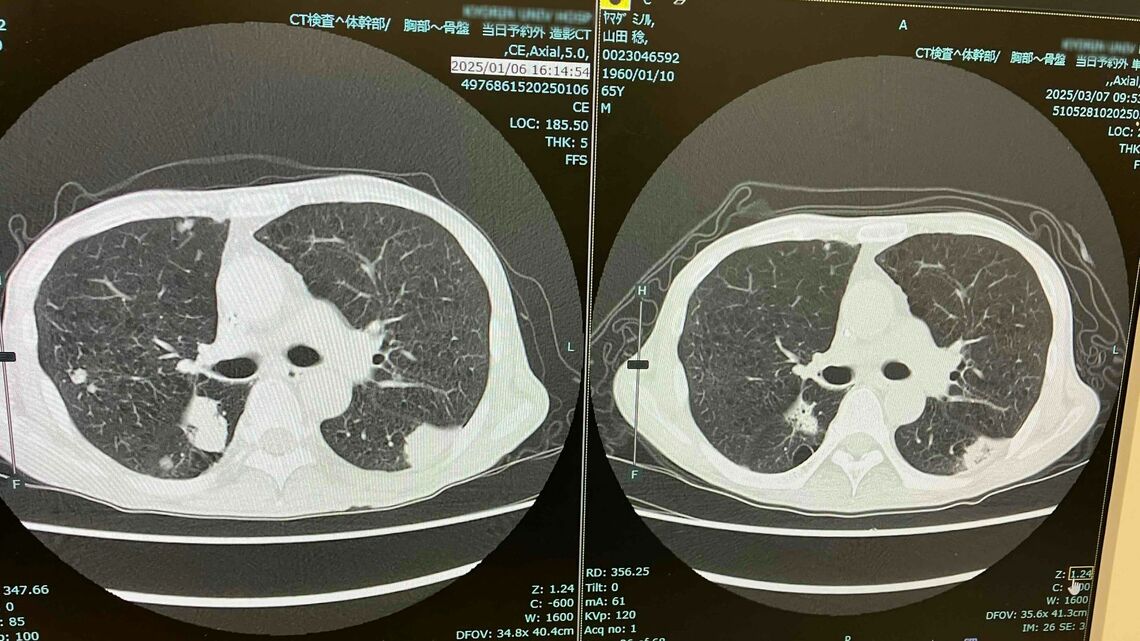

肺の腫瘍は明らかに小さくなった(左が1月/右が3月)